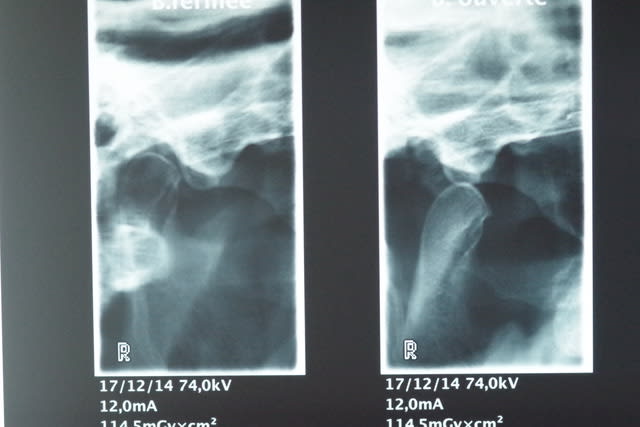

Voilà maintenant les radios:

2° Une radio des ATM D et G bouche ouverte et bouche fermée.

A priori je ne pense pas que ce patient souffre de luxation au vu des radios.

Qu'en pensez-vous ?

Il n'y a pas de luxation, c'est pas une surprise ça se voyait depuis le début.